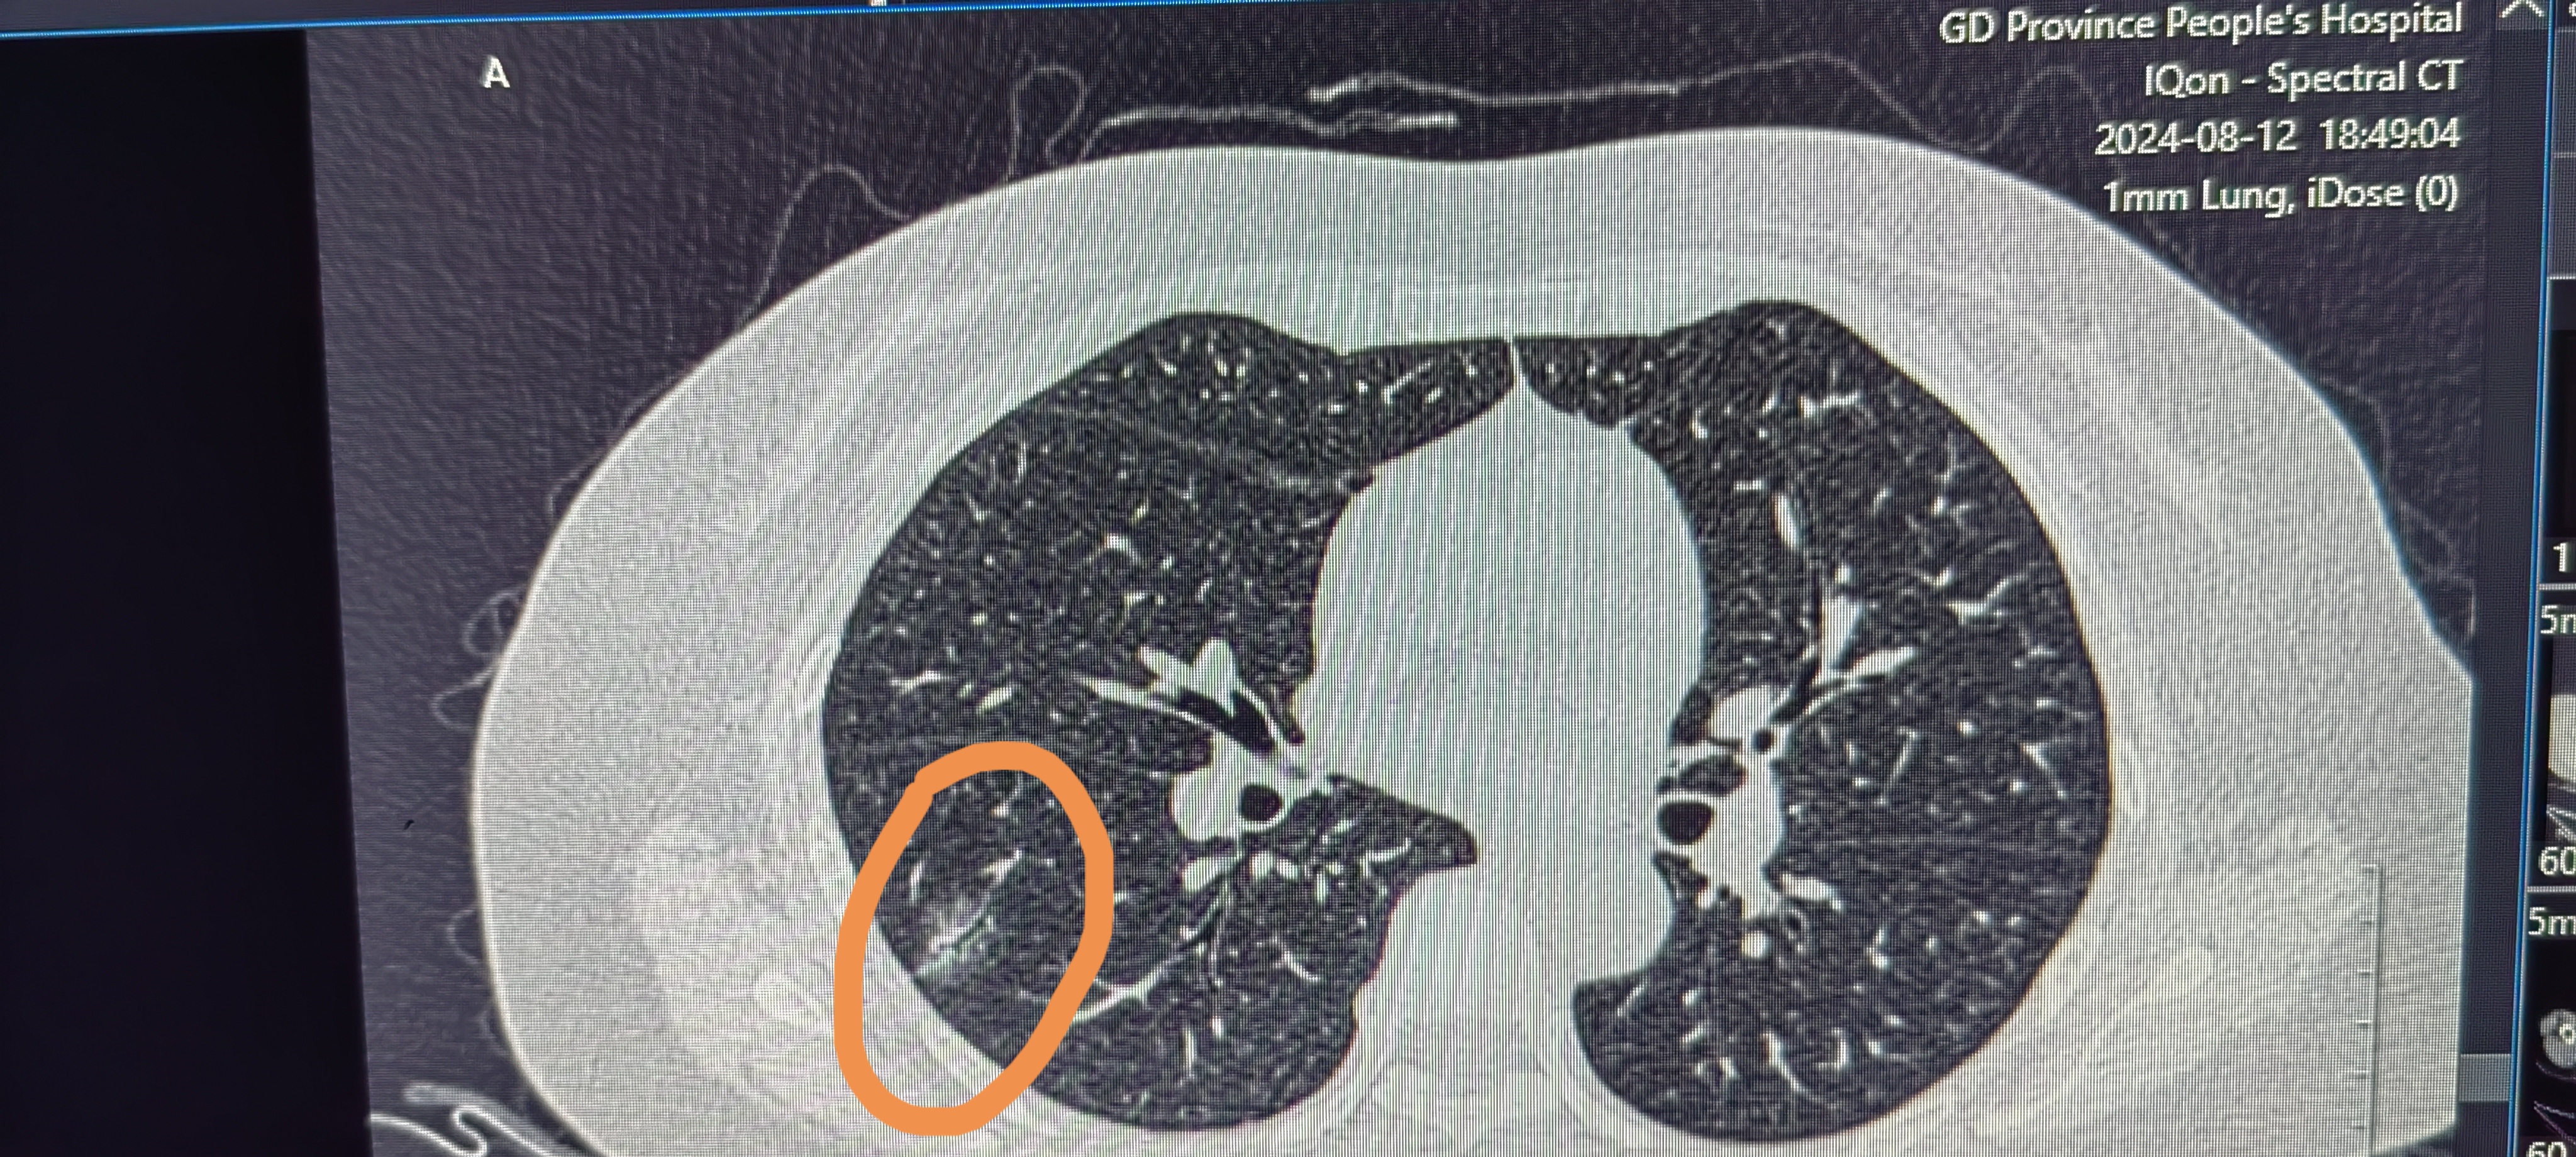

胸部ct提示右肺直径大小5mm肺结节老师们帮忙看看男性患者29岁吸烟史2